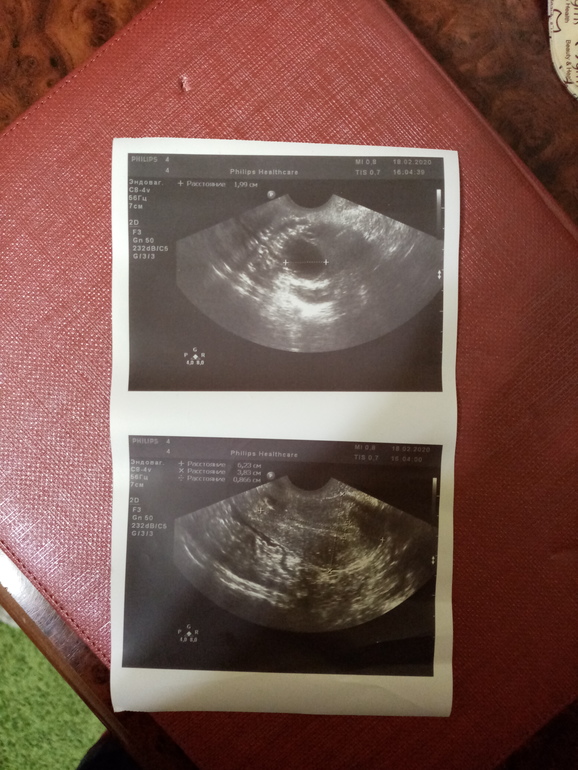

Сегодня 52 д. ц и 21 день задержки. 11 дней назад была на узи сказали киста(была в женской консультации) отправила результаты своему врачу, она прописала Норколут 10 дней. Вчера утром была последняя 💊. Сегодня ночью на работе очень болел живот. Пришла домой и сделала тест, это реагент? Как бы задержка уже большая и тест был бы уже гиперполосатый. Ну это я так вдрук на